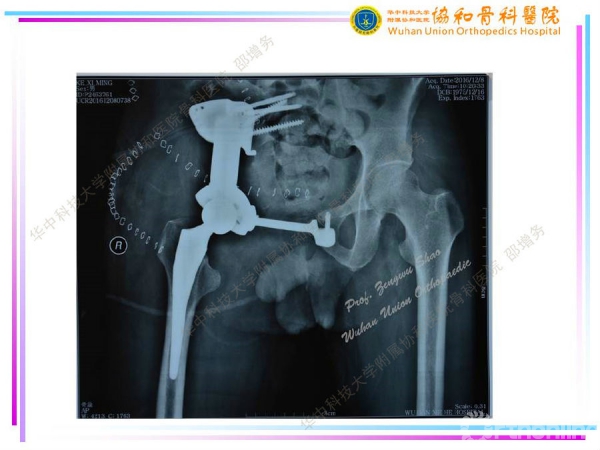

3D打印个性化半骨盆假体在骨盆肿瘤治疗中的应用

编者按--由于骨盆特殊的空间形态及周围复杂的解剖结构,骨盆肿瘤(尤其是髋臼周围肿瘤及骶髂部位肿瘤)的切除与重建一直是骨科医生面临的重大挑战之一。计算机技术、3D打印技术(3D打印骨盆三维模型、3D打印截骨导板、3D打印肿瘤假体)在骨盆肿瘤的应用,可大大提高截骨的准确性及假体的匹配度、缩短手术时间,降低假体相关并发症。2014年11月至2017年3月,华中科技大学附属协和医院骨科医院邵增务教授团队已顺利完成3D打印个性化板骨盆假体治疗骨盆肿瘤15例,近期效果满意,中远期效果有待进一步观察。